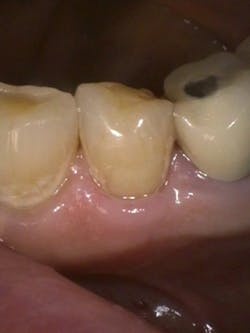

Figure 5: Class V cavity prep with laser. Photo courtesy of Jeff Rhode, DDS.

For the same reasons, the 10.6-micron CO2 laser has also been shown to damage the implant surface and increase the temperature of the adjacent hard and soft tissue surrounding the dental implant.4 Because of the difference in wavelength, absorption pattern, and introduction of water irrigation with the 9.3-micron CO2 laser (figure 1), it can now be used for hard-tissue applications. This laser has been used to prepare teeth for Class I–IV (figures 2–8) restorations without the concern of raising pulpal temperature and inducing necrosis. The laser has also been used as an alternative to conventional high-speed drills to prepare teeth for crowns, bridges, and veneers.